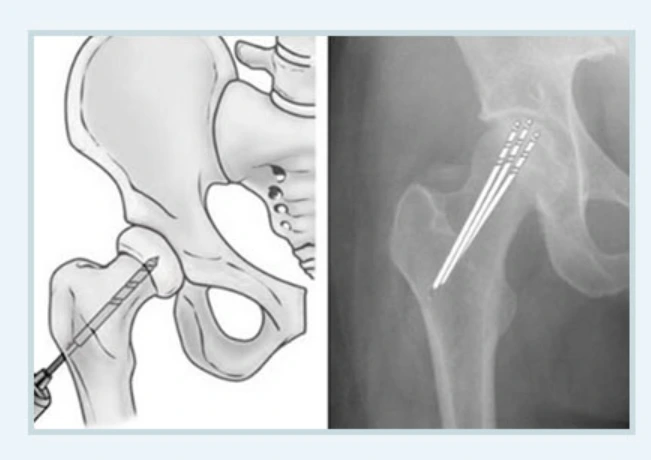

중심감압술

중심감압술.PNG

수강 내 압력을 감소시켜 혈관의 재생을 돕는 중심감압술은 자기 관절을 그대로 보존하는 치료입니다. 게다가 관절염의 진행을 방지할 수 있는 치료법이라서 대퇴골두가 무너지기 이전에 사용되는 수술이지요.